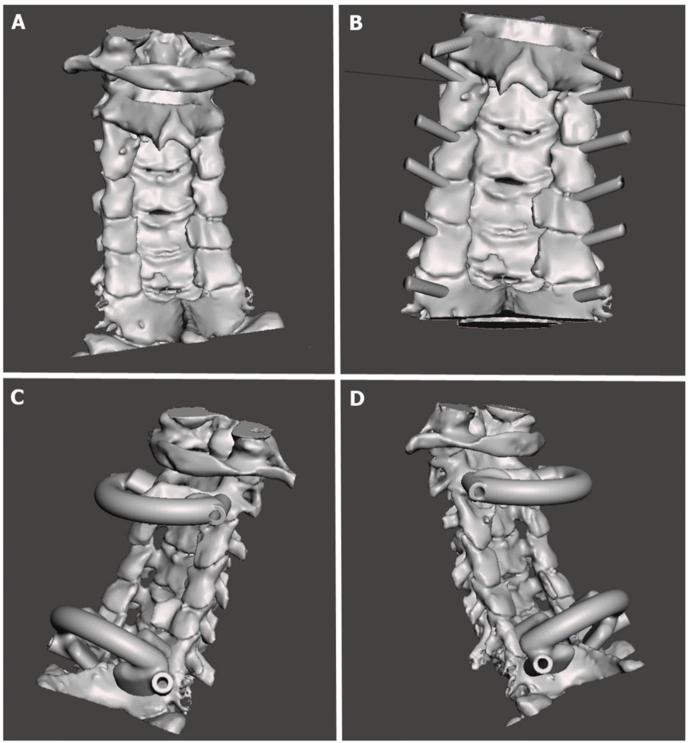

Case report: A 62-year-old male with a cervical spinal injury underwent emergency decompression at an external facility. Subsequent imaging revealed iatrogenic instability due to multi-level laminectomies (C3-C6). Preoperative CT data were processed using software (Mimics v14, MeshMixer) to design patient-specific templates, printed with a 3D Ultimaker 2 printer. These sterilized templates were used intraoperatively for navigation, aiding in transpedicular screw placement at C2, C7, and T1 levels, with lateral mass screws placed for C3-C6 using a freehand technique.